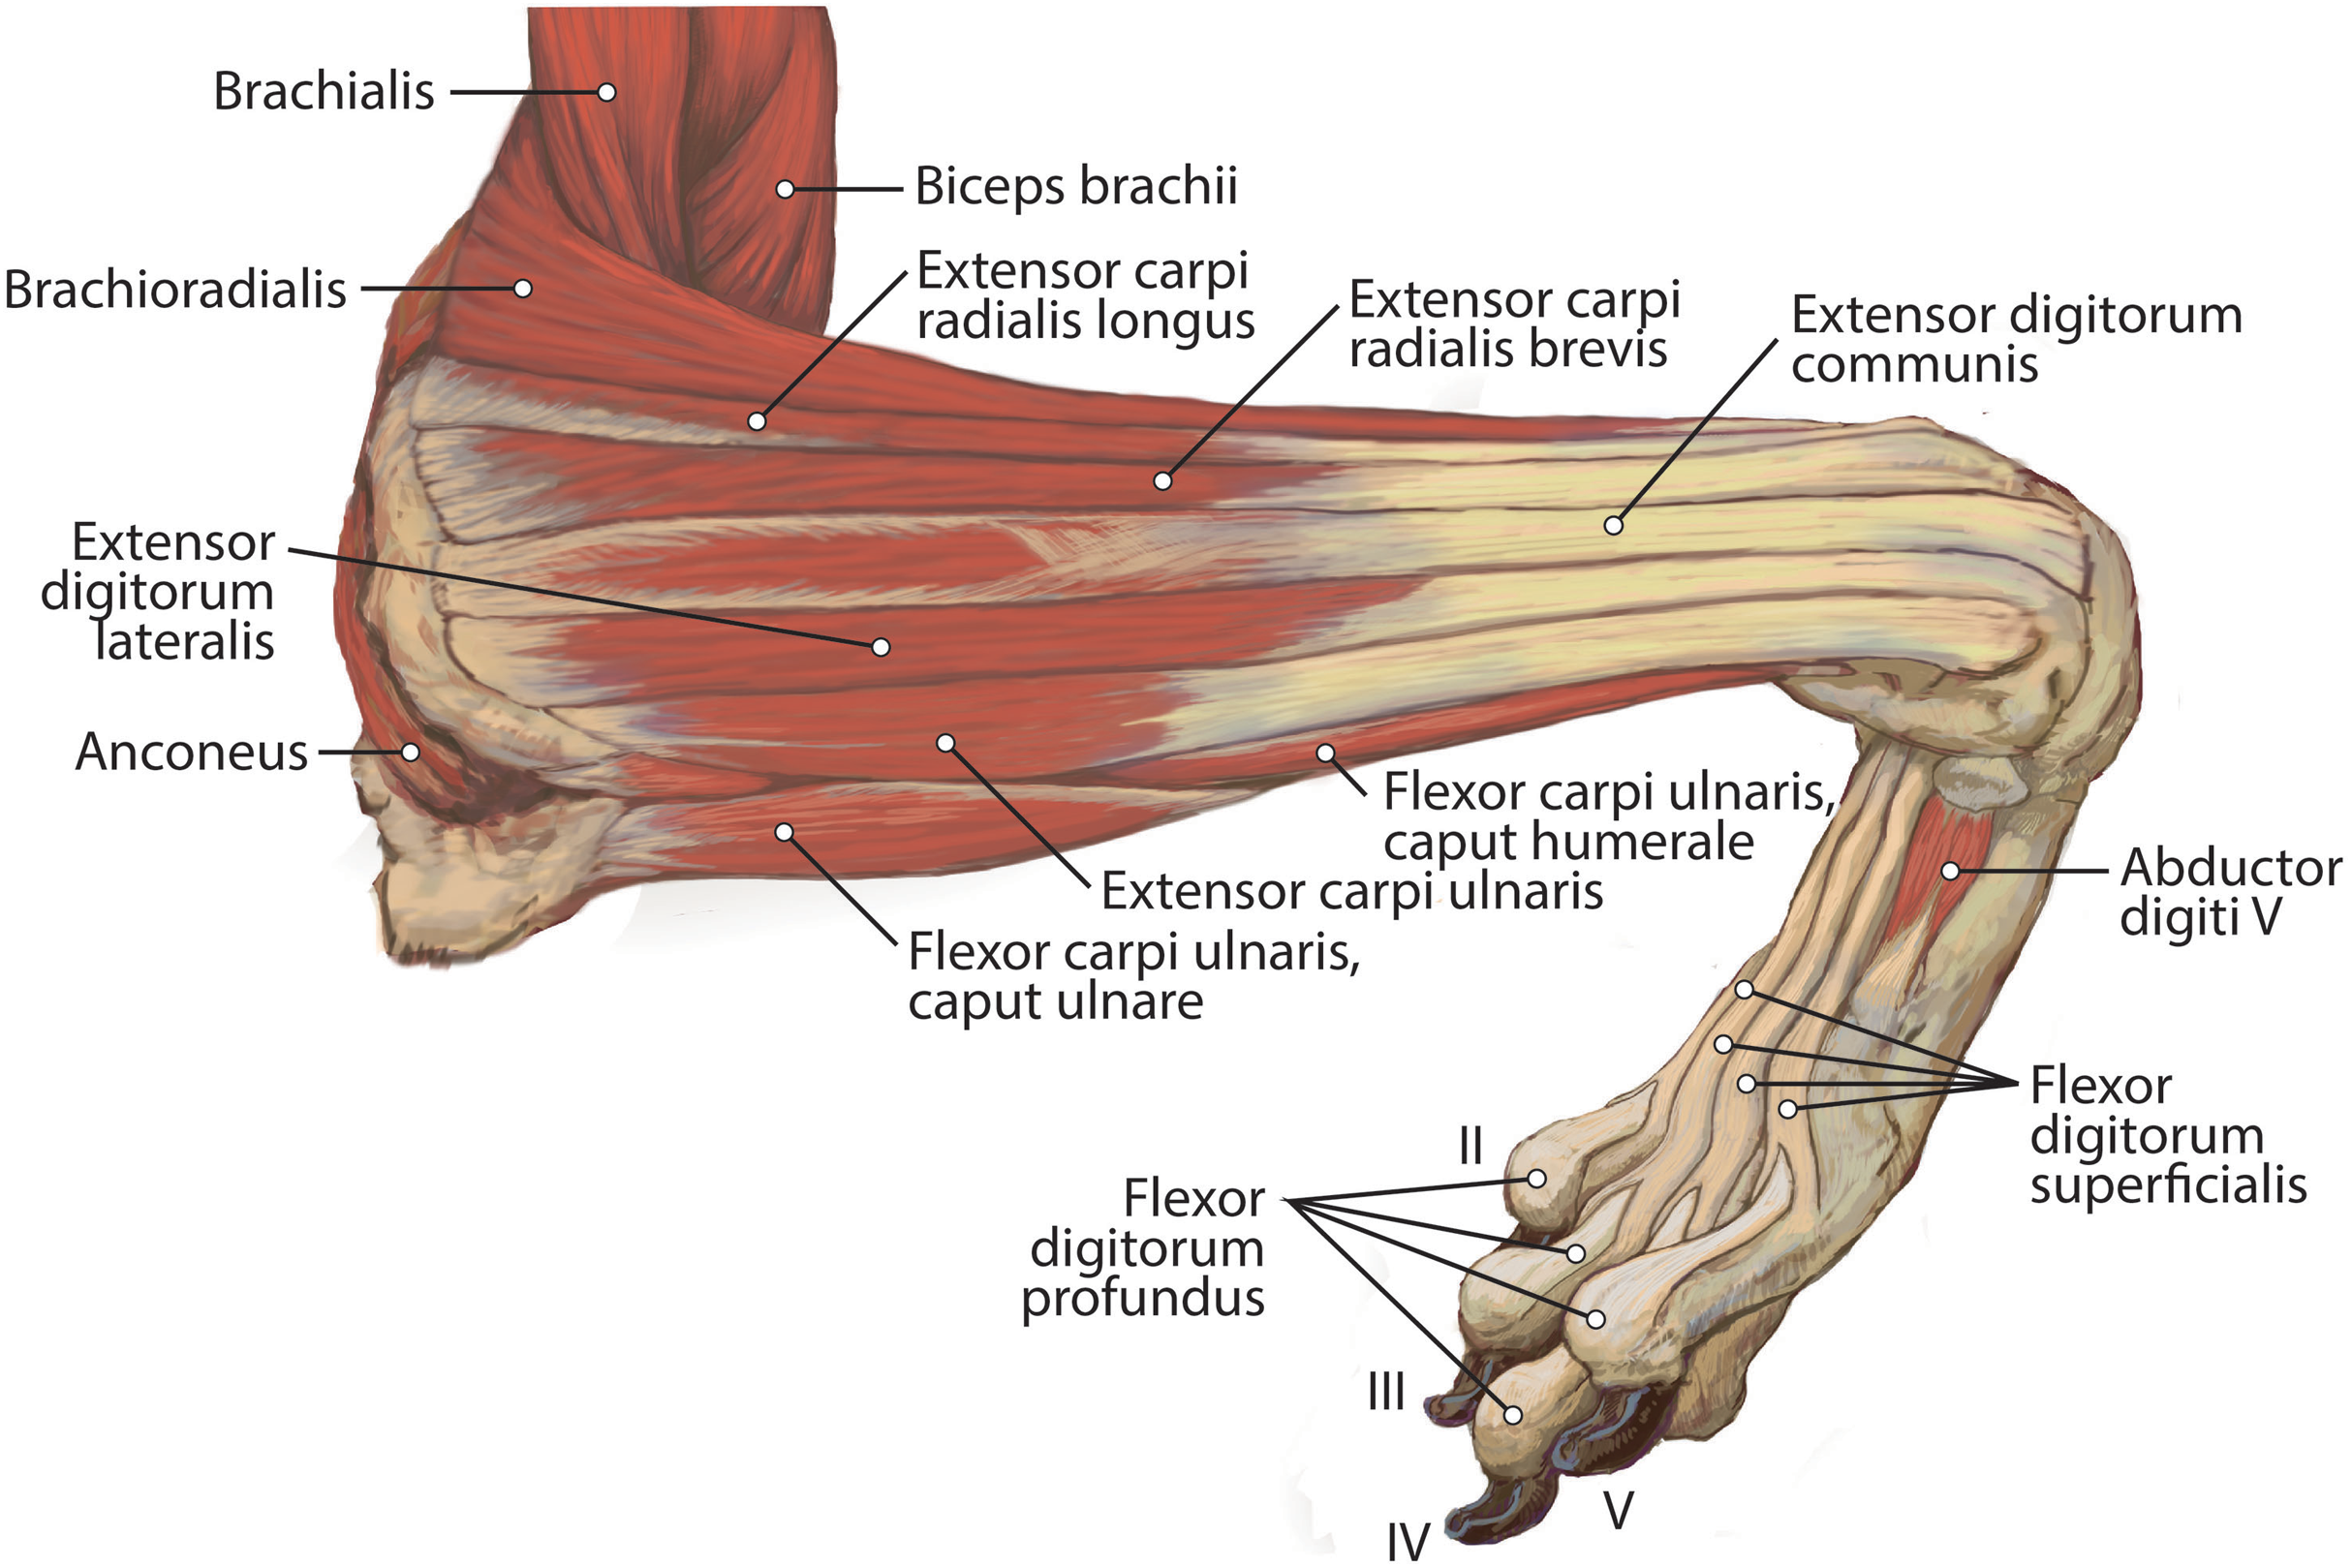

Анатомия и функции мышцы brachioradialis